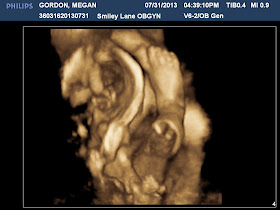

How is it already August 1?! And more important, I am just one week away from my THIRD trimester! Little Man (who has still yet to be named, but we're working on it!) is weighing in a week ahead of schedule at 2 lbs., 10 oz. Everything looks great on him, which is always a sigh of relief! He is definitely looking more and more like his sister did when she was born (below his pictures is one from the day she was born, just minutes old to compare). We never had the 4D ultrasounds done with her but my friend does them now and she wanted to play, so I made a special trip to her clinic to see our little one.

| That's his right foot for those that can't tell. It does a weird cross section of the bone, so it looks like it's been chopped off. His head is on the left, his toes almost touching his forehead. |